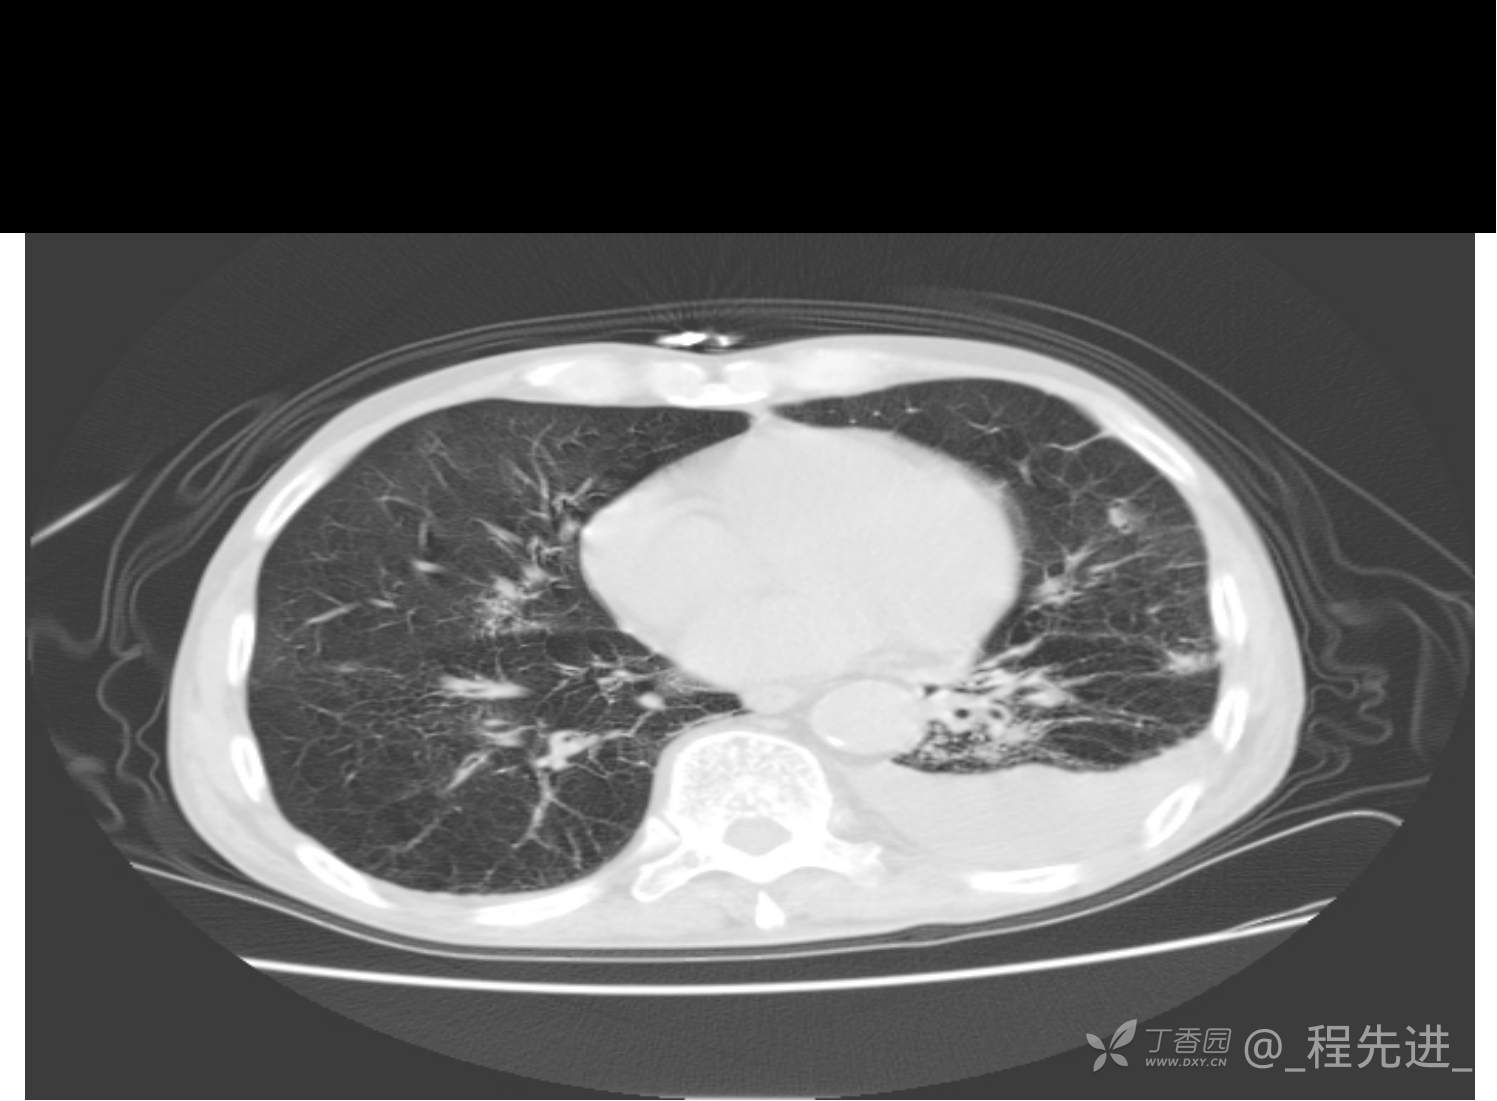

患者性别:男

患者年龄:81岁

简要病史:反复咳嗽、咳痰20余年,加重1周。两肺呼吸音低,可闻及散在干湿啰音。